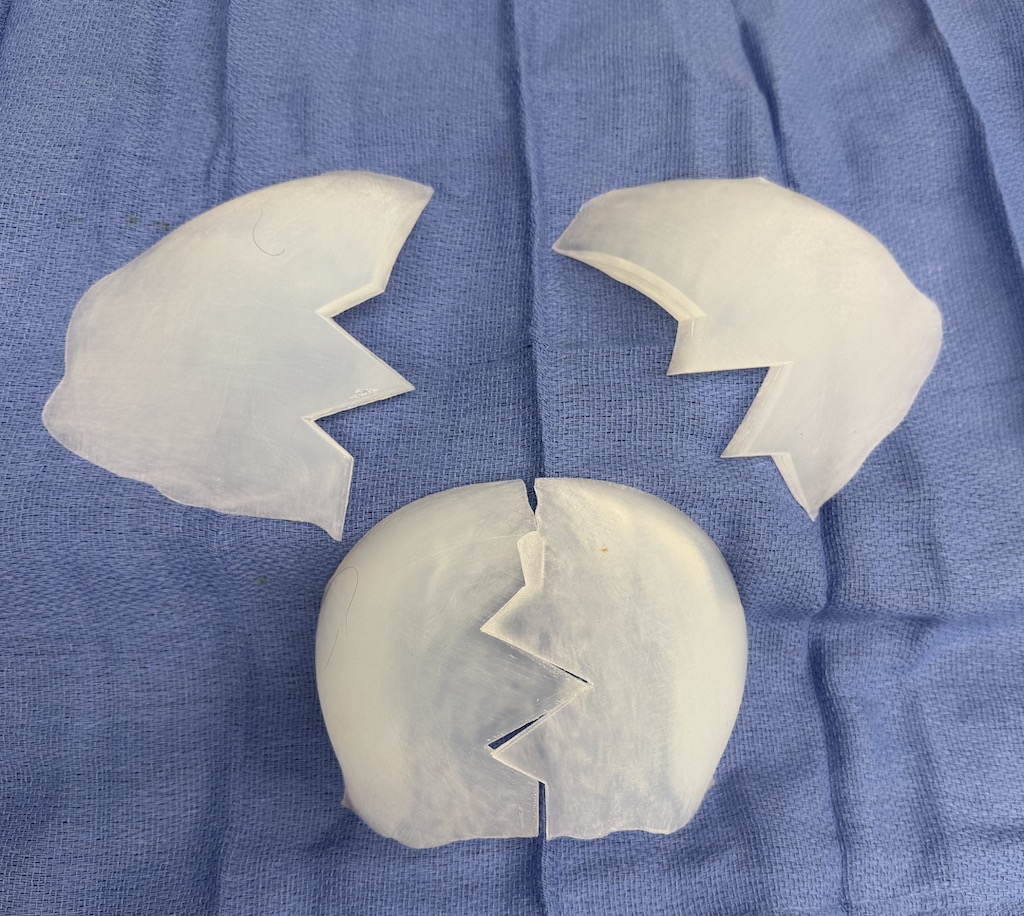

Desire for large overall skull augmentation procedure. Two piece custom skull implant designed with 250ccs volume.

1st stage scalp expander placed and inflated to 225ccs. 2nd stage two piece skull implant placed 4 months later.

Desire for large overall skull augmentation procedure. Two piece custom skull implant designed with 250ccs volume.

1st stage scalp expander placed and inflated to 225ccs. 2nd stage two piece skull implant placed 4 months later.